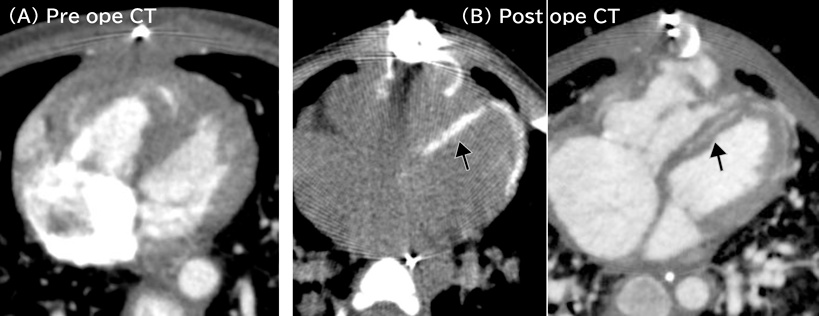

Acute postoperative course was unstable mainly due to right ventricular diastolic dysfunction. Central venous pressure, however, decreased from 20 mmHg to 13 mmHg, so that chest was closed 6 days later. Her hemodynamic condition gradually improved thereafter. We intended to arrange endotracheal extubation, but lactic acidosis and peripheral edema recurred. Cardiac computed tomography scanning at 16 days after the operation showed no aortic arch obstruction, no left ventricular outflow tract obstruction, mild stenoses of the bilateral branch pulmonary arteries, and circumferential myocardial calcification around the left ventricle (Fig. 1). Cardiac catheter examination at 21 days after the operation showed that left and right ventricular end-diastolic pressures were 19 mmHg and 14 mmHg, respectively (Table 1). Pulmonary-to-systemic blood flow ratio was 2.1 due to residual VSD. Therefore, removal of the intraventricular tunnel and downsizing of the right ventricle-to-pulmonary artery conduit were carried out on the day 33 after the Yasui operation. The chest was closed 3 days later when central venous pressure decreased to 10 mmHg. Since then, her hemodynamic condition had rather deteriorated. Cardiac catheter examination 18 days after the takedown revision revealed that both left and right ventricular end-diastolic pressures were equally 29 mmHg (Table 1).

Fig. 1 Cardiac CT imaging. (A) Preoperative image shows no calcification in the myocardium. (B) Circumferential myocardial calcification was obvious within the left ventricular wall (indicated by black arrows) 16 days after the Yasui operation. Calcification is so extensive that the ventricle is most likely to have diastolic dysfunction.

Pre ope, before the Yasui operation; Post ope, after the Yasui operation